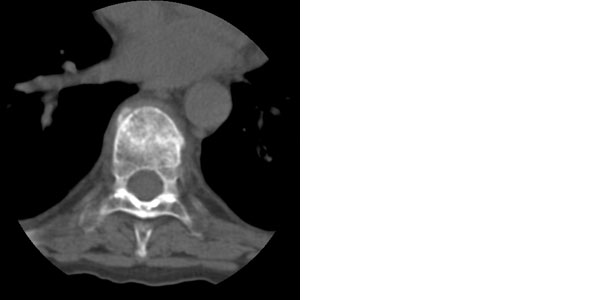

女性 45岁 患肾病综合症1年 有长期使用激素史 现诉背部疼痛。

椎弓根无破坏,椎间隙正常存在,椎旁未见软组织肿块,结核及转移可见除外吧,考虑压缩性骨折

骨质疏松所致的压缩性骨折

上不着村下不着店,胸骨也未见到,很难定位。结合病史考虑为骨质疏松所致多发性胸椎骨折合并节段性胸髓损伤。

考虑骨质疏松所致多发压缩性骨折。